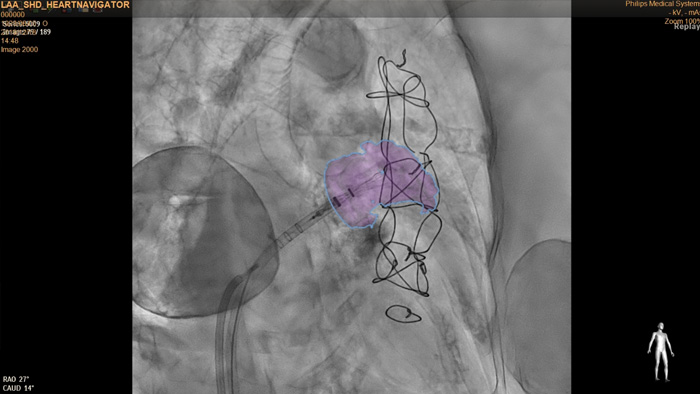

The HeartNavigator is a CT planning and live overlay guidance solution using automatic heart model segmentation of anatomy to improve ease of use, speed and reproducibility. In LAA occlusion, HeartNavigator enables: